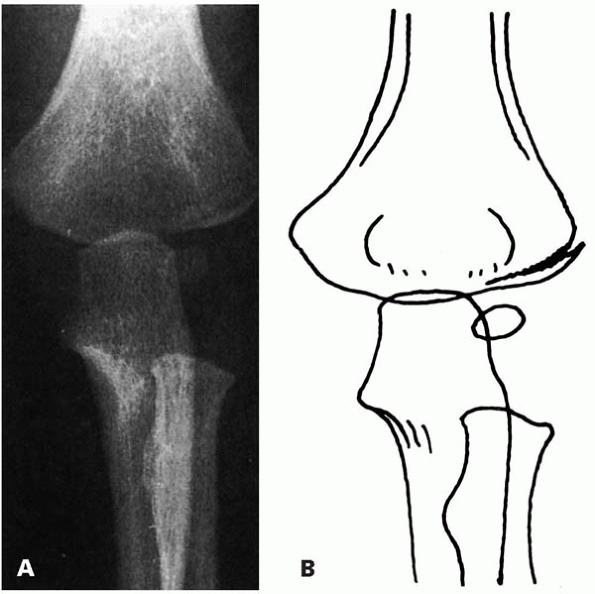

▪ FIGURE 6-2 A:

Type A fracture. Fracture through the lateral humeral condyle with a minimal gap laterally. The fracture cannot be followed to the epiphyseal cartilage. B: Outline of the radiograph. (Reprinted with permission from Finnbogason T, Karlsson G, Lindberg L, et al. Nondisplaced and minimally displaced fractures of the lateral humeral condyle in children: a prospective radiographic investigation of fracture stability. J Pediatr Orthop. 1995;15(4):422-425.) |

nonoperative treatment. A prospective investigation of 112 lateral

condyle fractures with ≤2mm of displacement treated with splinting

reported that if the fracture line cannot be followed to the epiphysis,

the fracture is stable and not at risk for displacement1 (Fig. 6-2).